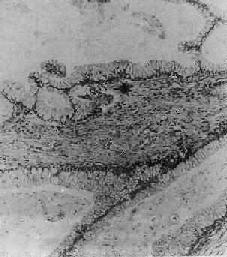

图13-17 卵巢乳头状浆液性囊腺癌

呈细乳头状结构,癌细胞多层,异型明显,乳头间质稀少